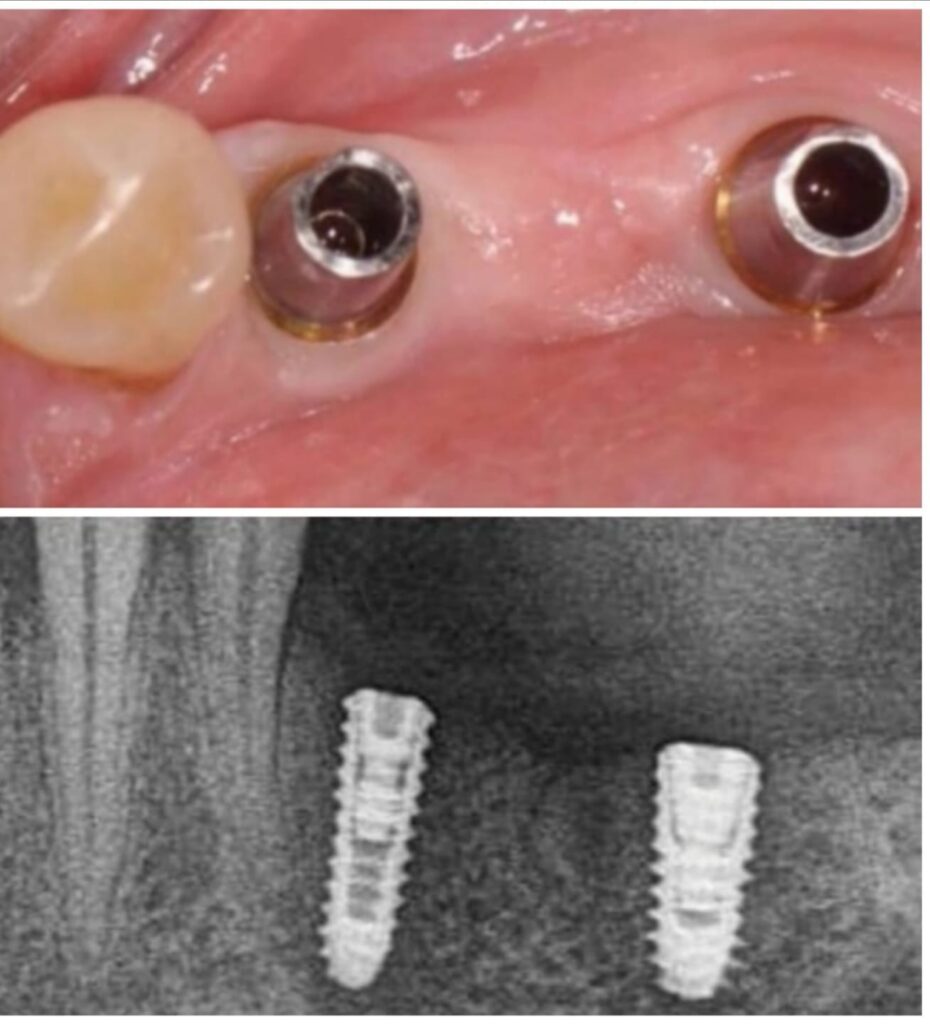

تضيف اجهزه البانوراما الداخلية واجهزة التصوير ثلاثية الأبعاد بعدًا آخر لتقنية الزرع من خلال صورها الدقيقة للفك والأسنان. هذه الدقة ضرورية لتخطيط ووضع الغرسات. يوفر تقييمًا دقيقًا للبنى التشريحيه مثل الأعصاب وجذور الأسنان والجيوب الفكية ومعرفة طبيعة العظم وكثافة وما إلى ذلك ، مما يمنع أي احتمال للفشل الذي يحدث بسبب التشخيص الخاطئ. تم تجهيز مراكز الزرع لدينا بهذه الآلات المتطورة ، مما يمكننا من تنفيذ كل حالة من حالات الزرع بدقه عاليه وأعلى درجات النجاح.